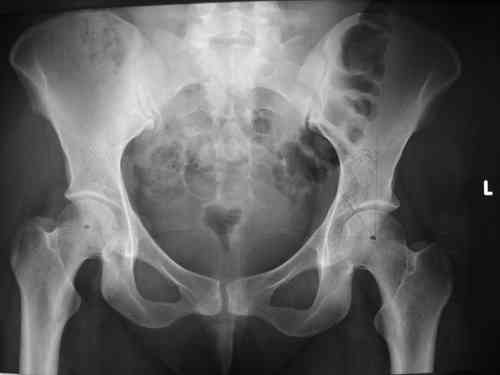

Re: Застарелое повреждение таза

прилагаю пример с такой же давностью травмы, репонировали аппаратом